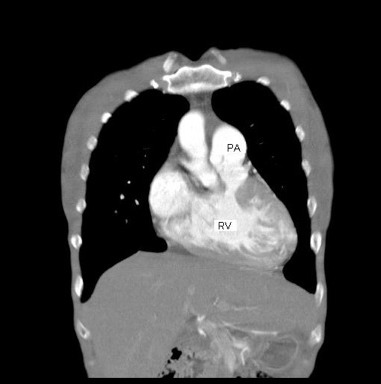

図5: 造影CT検査、右室流出路狭窄による肺動脈狭窄を認める。肺動脈弁は正常のようにみえる。